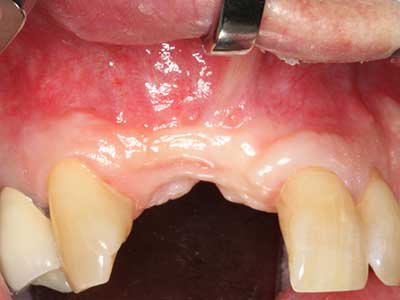

Knochengewebe ist nicht nur rein mineralisch, sondern auch in wesentlichen Anteilen aus Kollagenfasern aufgebaut. Dies gewährleistet neben einer guten Druckfestigkeit eine gewisse Flexibilität, welche für die Durchführung von Augmentationen genutzt werden kann. Bei der klassischen Expansionsplastik im Sinne eines Bone Splittings wird der atrophierte Kieferkamm in seiner Längsachse gespalten und nach Erreichen einer ausreichenden Osteotomietiefe vorsichtig aufgedehnt (Abb. 13-16), idealerweise ohne den Kiefer wesentlich zu deperiostieren (Brugnami, Caiazzo et al. 2014, Stricker, Fleiner et al. 2014). Bewährt haben sich Schrauben- und Plattensysteme mit zunehmender Expansionsdistanz, um die beiden Knochenlamellen unterhalb der Bruchschwelle voneinander zu distanzieren. In der Regel werden Restknochenbreiten von mindestens 3-4 mm gefordert (Chiapasco, Zaniboni et al. 2006), um eine ausreichende Flexibilität und knöcherne Bedeckung der einzubringenden Implantate zu gewährleisten. Ggf. kann eine ein- oder beidseitige vertikale Entlastungsosteotomie die Flexibilität verbessern. Als Alternative zur klassischen Technik wurde eine Kombination mit weiteren augmentativen Techniken vor allem auf der bukkalen Seite beschrieben.

Mittels Piezosägen erfolgt die Anlage des Splittings besonders schonend und ohne wesentliche Dimensionsverluste, so dass sich keine signifikanten Unterschiede von Implantaten im gesplitteten Kiefer im Vergleich zum nicht defizitären Alveolarkamm gezeigt haben (Chiapasco, Zaniboni et al. 2006, Danza, Guidi et al. 2009). Gerade beim lokal begrenzten und tiefen Splitting ist jedoch stets auf eine ausreichende Wasserkühlung zu achten, um thermische Belastungen in den apikalen Osteotomiebereichen zu vermeiden.